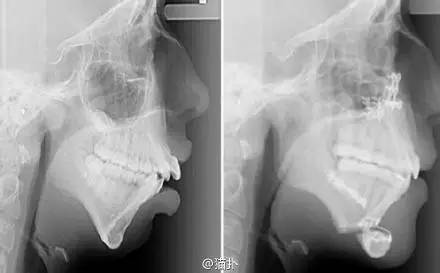

英国20岁的女孩艾丽·琼斯先天面部畸形,8岁时下巴就停止生长,牙齿也因此排列不齐。历经六年时间,在接受了牙齿矫正和下巴重建手术后,她的面容发生了很大的变化,也因此变得更自信。

其实也就是简单地下巴截骨前移,变化就这么大了